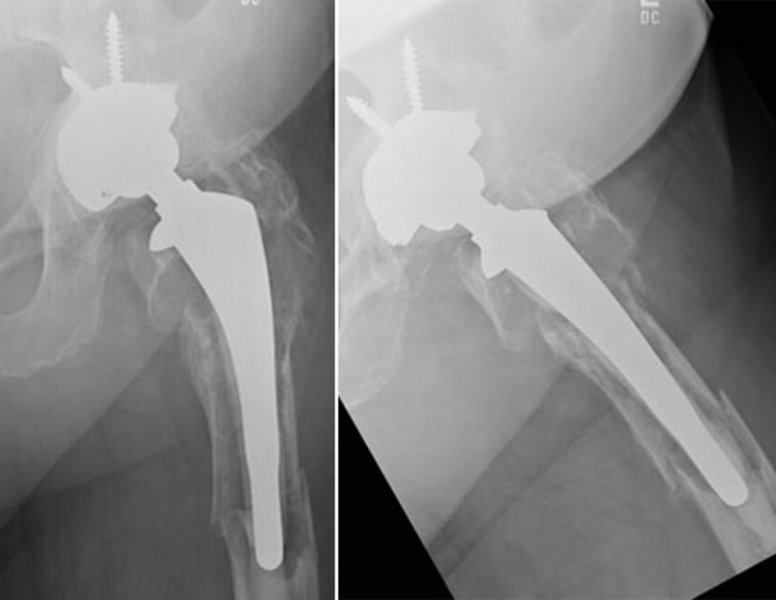

In den überwiegenden Fällen treten nach zunächst guter Funktion von Knie- u. Hüftendoprothesen Schmerzen auf, die vom Patienten erstgenommen werden sollten und Anlass zu einer klinischen sowie Röntgenuntersuchung geben sollten. Hierbei können Lockerungszonen und Gebiete von aufgelöstem Knochen um die Prothese herum erkannt werden. In Einzelfällen kann jedoch eine schmerzfreie Funktion der Prothese vorliegen, es sind jedoch röntgenologisch schon deutliche Veränderungen erkennbar, die schließlich sogar zum Ausbrechen der Prothese oder Brechen des Knochens führen können (Abb. 1).

Jeder Prothesenwechsel erfordert ein individuelles Vorgehen, das nur teilweise standardisiert ist. Die Wechselendoprothetik erfordert große Erfahrung und setzt ein umfangreiches Arsenal an verschiedenen Endoprothesentypen voraus, um während der Operation auftretende Komplikationen zu beherrschen. Wir verwenden im Hüftbereich verschiedene Schäfte, die z. T. modular aufgebaut und den individuellen Gegebenheiten angepasst werden können. Die Defektzonen und gebrochenen Anteile werden mit langen Spezianschäften überbrückt (Abb. 2). Auch im Bereich der Hüftpfanne müssen die oft großen Defekte teilweise mit Knochen oder mit Stützschalen sowie Spezialimplantaten wieder aufgebaut werden.